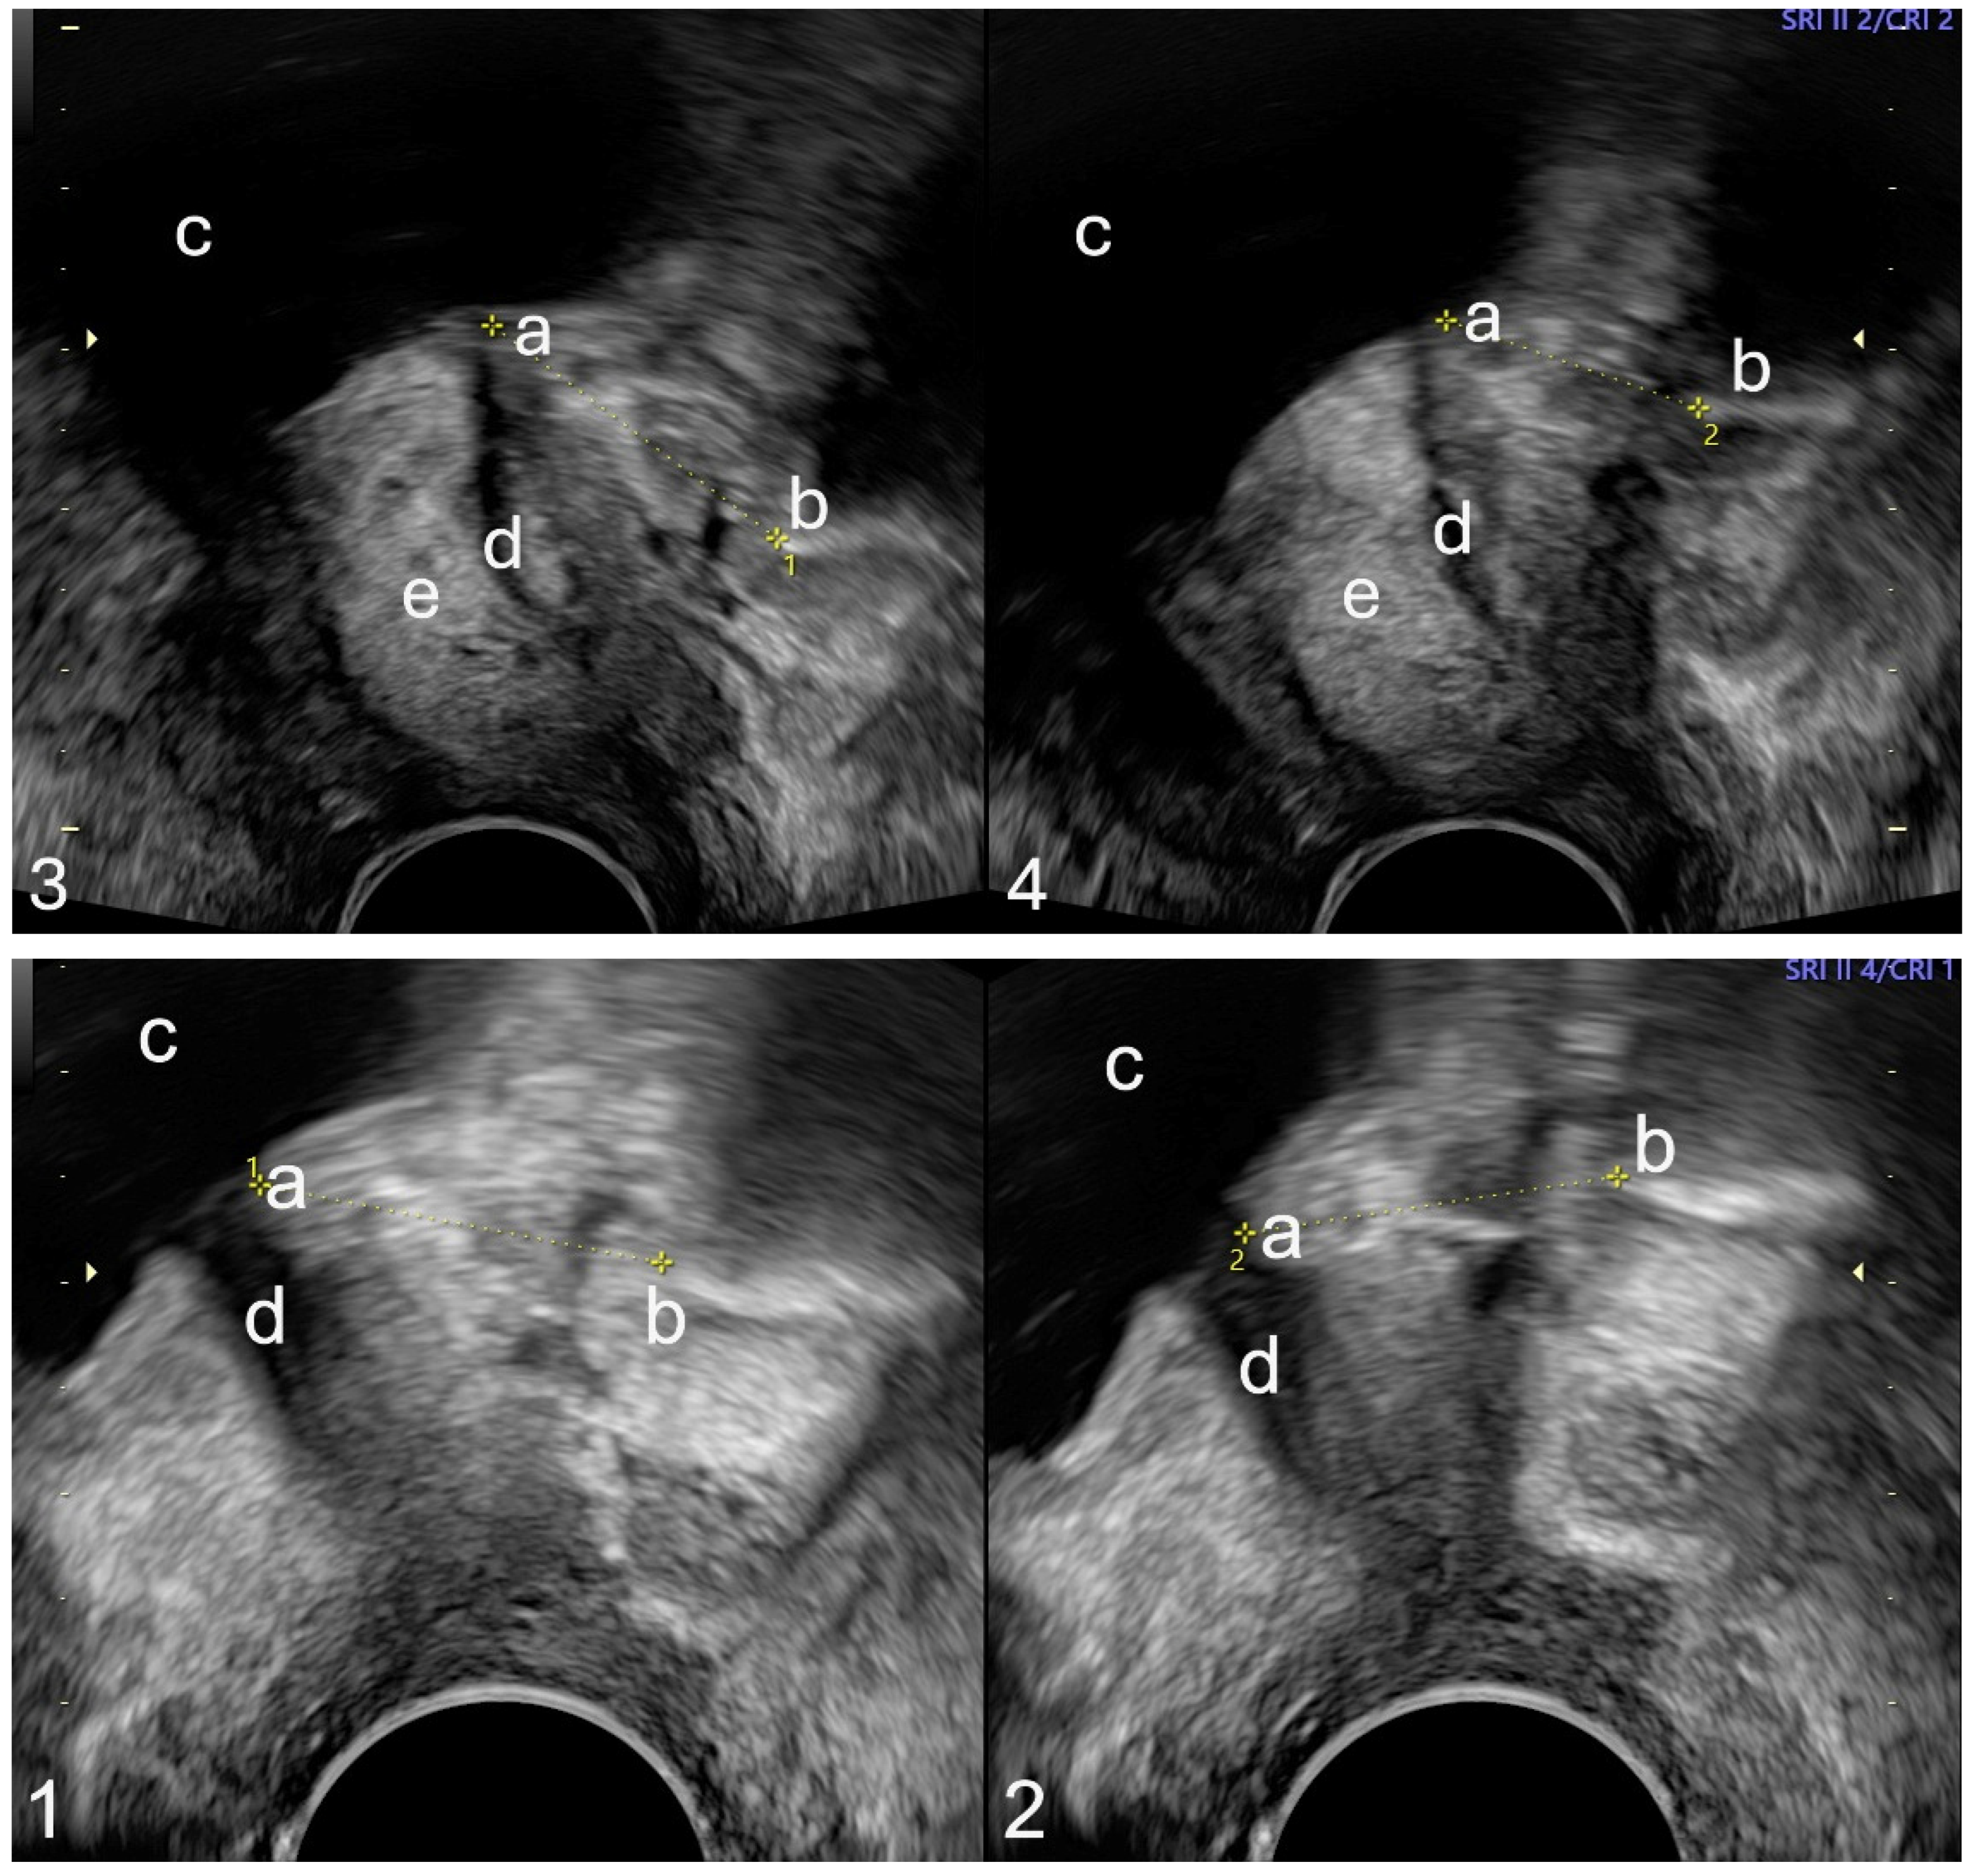

2. Materials and Methods